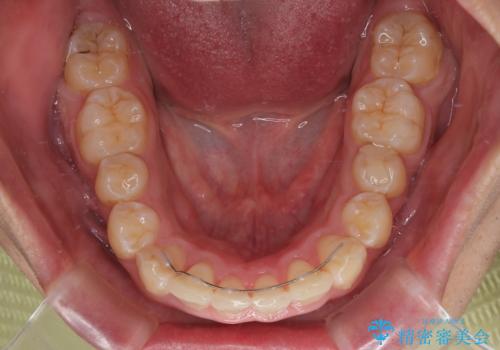

- デコボコと奥歯の咬み合わせのズレを気にして来院された患者様です。

骨格的に、下顎が右側にずれており、左側の咬み合わせに鋏状咬合などのアンバランスが生じている状態でした。

また、上顎前歯に欠損が1本あり、上下ともに前歯部に叢生が認められ、下顎前歯の大半が隠れてしまうほどの過蓋咬合も認められました。

咬合平面を平坦にしながら前歯の咬み合わせを挙上し、デコボコと鋏状咬合も改善していくこととしました。

骨格的な左右差が大きかったため、上下の正中のズレや、左右奥歯の咬み合わせなどは妥協的な仕上がりとなりました。